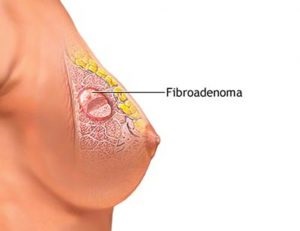

Cele mai multe femei sunt interesate de fibroadenom cât de periculos și cum să-l detecteze? Aceasta este o tumora benigna, care poate dezvolta livrarea asimptomatic și nu orice disconfort pentru pacient. Cel mai adesea bulgărele detectate cu mamografie sau de auto-examinare. Fibroadenom - o formație strânsă, nu lipit de piele. Când atingeți nu apare durerea. Tumora poate avea dimensiuni diferite și au o mare mobilitate. Din țesutul glandular separă capsula ei strans.

Există mai multe tipuri de fibroadenoame, care diferă în mărime, formă, și dezvoltarea caracterului. Complet tumori mature au un înveliș protector gros și o textură elastică, comparabilă cu bilă elastică. fibroadenoma matur caracterizată de o creștere lentă. Ele sunt o lungă perioadă de timp să rămână în mărime completă și nu provoacă îngrijorare special femeile. fibroadenoma imatură diferite densitate mai mică. Este predispus la dezvoltarea rapidă, rezultând o deformare a prostatei. tumora mature gasit cel mai frecvent la femeile în vârstă de peste 25 de ani, caracteristic imatur al fetelor care intră la pubertate. tumora Imature poate creste la fel ca și dispar fără tratament. Femeia se confruntă cu problema creșterii rapide a fibroadenoame și independentă de definiția sa.